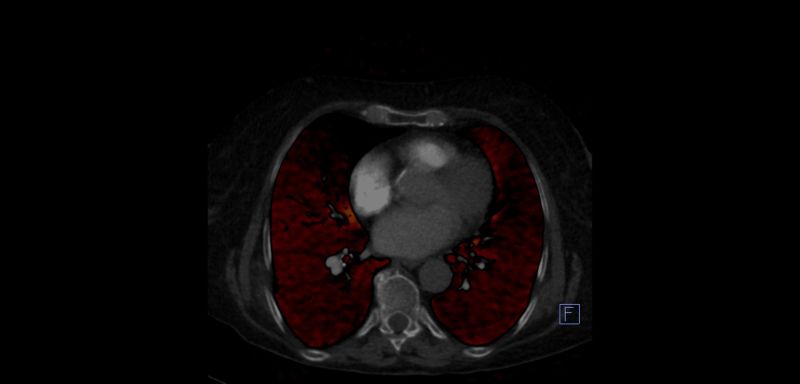

OLGU 2.

Normal tomografide PTE demostre edilememiştir. Dual BT Perfüzyon BT ile Kronik Pulmoner Emboli'si olan olguda sağ orta lobta perfüzyon defekti gözlenmektedir.